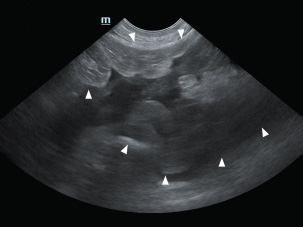

An 11-year-old intact male Siberian Husky was presented in acute hypovolemic shock. On physical examination, the patient was lethargic and exhibited tachycardia, tachypnea, and hypotension, with a recorded systolic/diastolic blood pressure of 58/31 mmHg. Abdominal radiographs were not diagnostic due to the loss of serosal detail secondary to intra-abdominal fluid accumulation. Hematologic evaluation revealed microcytic (mean cell volume, 58.4 fL; reference range, 61.6–73.5 fL) and normochromic (mean corpuscular hemoglobin concentration, 30 g/dl; reference range, 32–37.9 g/dl) anemia, with a packed cell volume (PCV) of 28.5% (reference range, 37.3%–61.7%). Additional abnormalities included hyperglycemia (231 mg/dl; reference range, 70–143 mg/dl), hyperamylasemia (4543 U/L; reference range, 500–1,500 U/L), hyperlipasemia (5,683 U/L; reference range, 200–1,800), and elevated D-dimer concentration (2 mg/dl; reference range, 0–0.3 mg/dl). Abdominal ultrasonography identified a well-circumscribed, round, lobulated mass measuring approximately 10 cm in diameter, located caudal to the stomach (Fig. 1). A large volume of peritoneal fluid was also present within the abdominal cavity (Fig. 2). Compared to the anechoic urine within the bladder, the peritoneal fluid appeared hyperechoic. Fluid collected via abdominocentesis showed a PCV of 28% (reference range, 37.3%–61.7%). Thoracic radiographs showed no evidence of pulmonary metastases or thoracic abnormalities.

Fig. 2. A large amount of echogenic peritoneal fluid (white arrowhead), indicative of bleeding, was detected in the abdominal cavity.